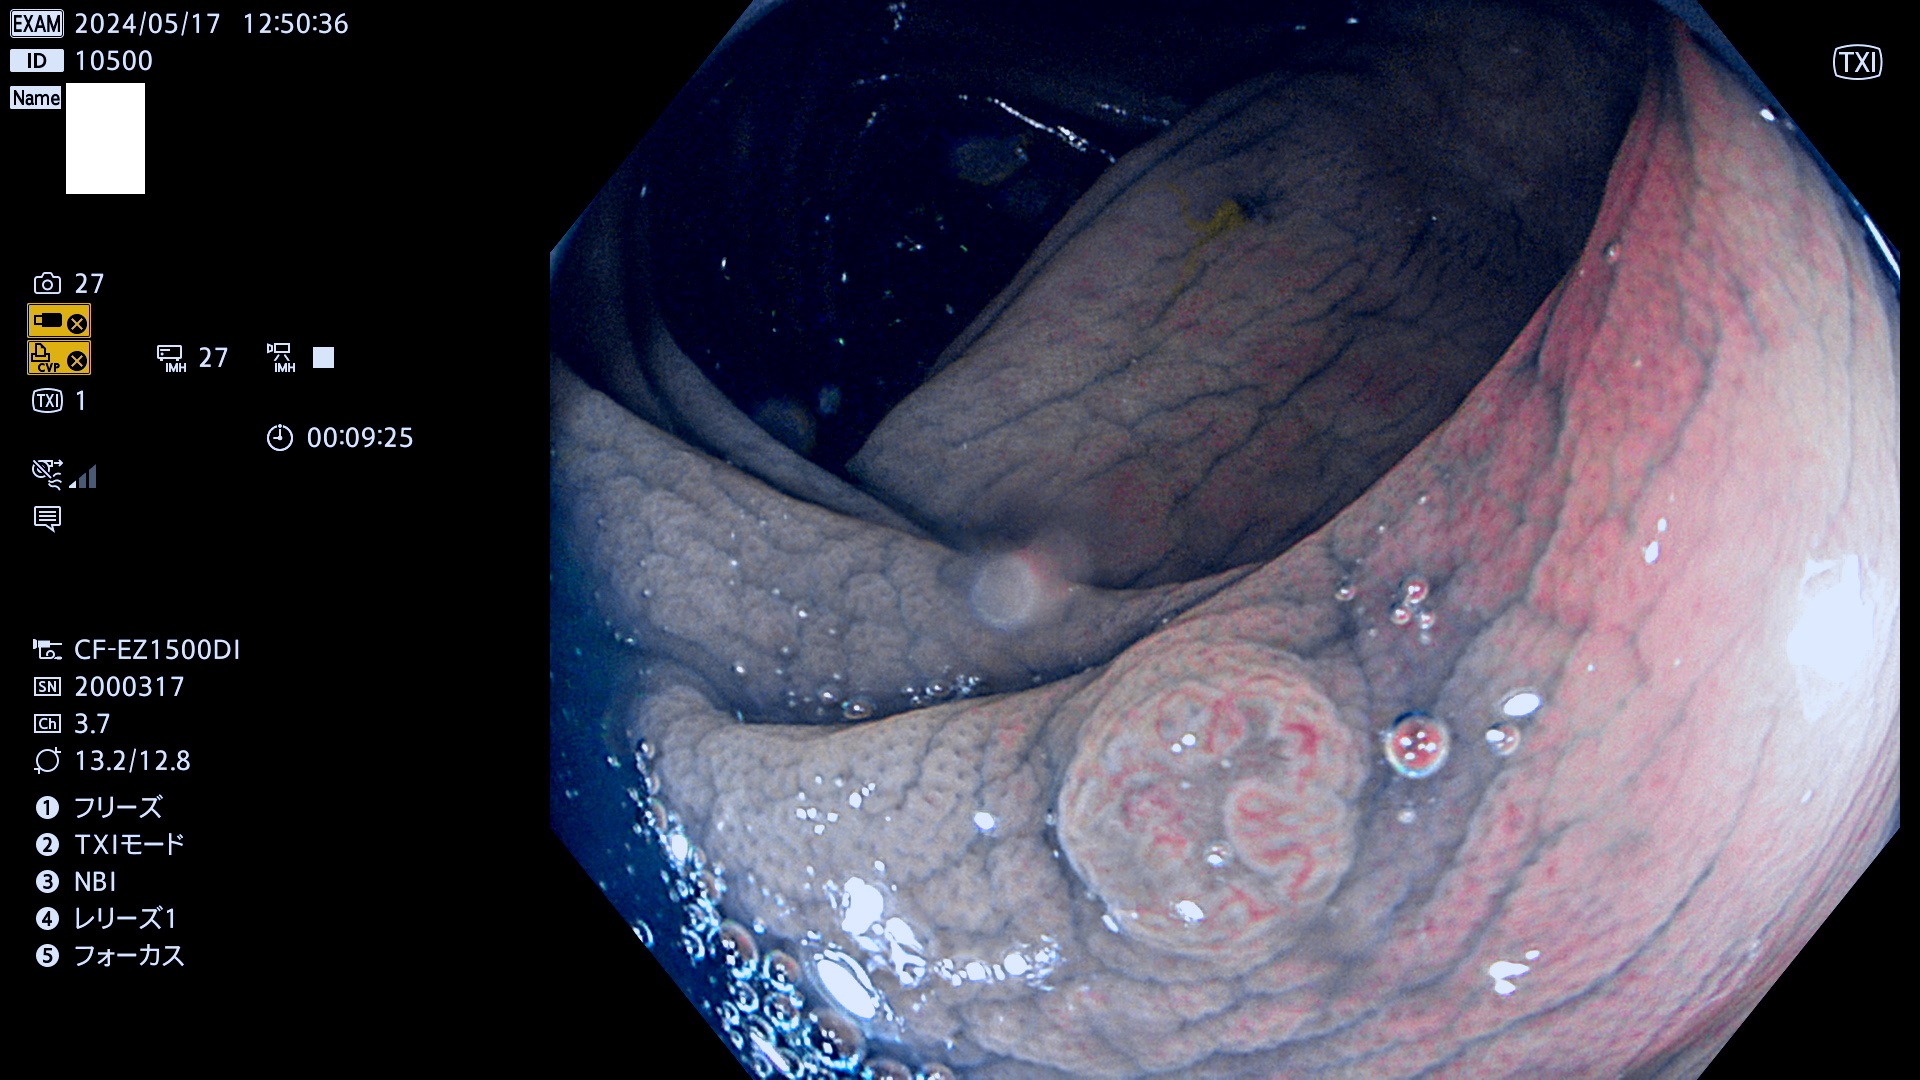

表面型腺腫(Flat Adenoma)の中で、完全に平坦な物をUb、陥凹している物をUcと呼びます。平坦隆起型(Ua)よりも、発見が難しく危険な病変です。

毎週の検査(木・金・土・日)に発見されたUb、Uc型・腺腫を、その週の日曜の夜にUPし1週間、提示します。

抽出の対象期間 2024年5月16日〜5月19の4日間(40件の検査)10件 (10/40=25%)